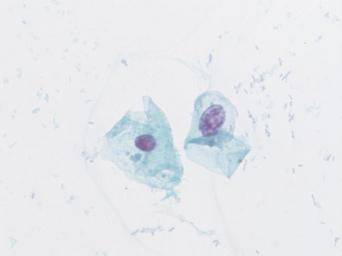

Keywords: lesión intraepitelial escamosa de bajo grado lesiónintraepitelialescamosadebajogrado citología de cuello uterino citologíadecuellouterino citología exfoliativa ginecológica citologíaexfoliativaginecológica citología de cribado citologíadecribado citología anatomía patológica anatomíapatológica bethesda 2001 bethesda2001 osuna cérvix uterino cérvixuterino hpv españa screening lsil enfermedades de transmisión sexual enfermedadesdetransmisiónsexual imágenes de citología ginecológica imágenesdecitologíaginecológica papanicolaou test de papanicolaou testdepapanicolaou tinción de papanicolaou tincióndepapanicolaou white background drawing Células con núcleo y citoplasma aumentado de tamaño, núcleos irregulares, como plumosos, tendencia al color naranja de muchas células, halos en algunos casos, núcleos dobles en otros, algunos núcleos hipercromáticos. Células con núcleo y citoplasma aumentado de tamaño, núcleos irregulares, como plumosos, tendencia al color naranja de muchas células, halos en algunos casos, núcleos dobles en otros, algunos núcleos hipercromáticos.